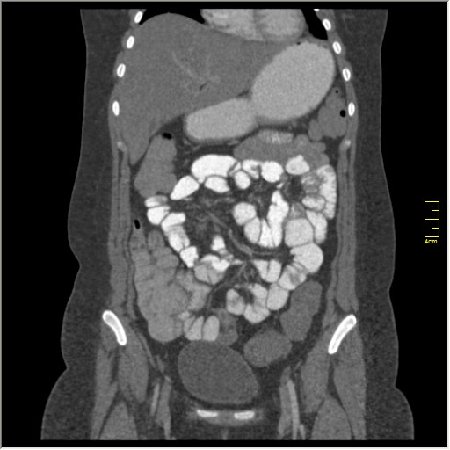

КТ энтерография

Демонстрационные изображение, оцените возможности метода! Толщина среза реконструкции 0.5-1 мм.